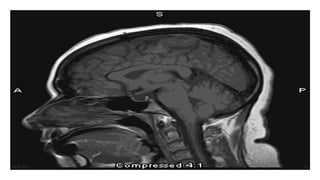

Diagnosis:

CT Scan (VH OR VS ratio: less than 0.5 is considered normal)

MRI